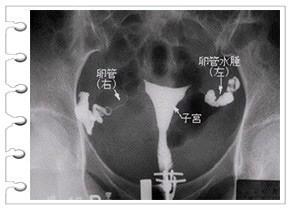

问题 图为子宫输卵管碘油造影示图,行造影术的禁忌证是 ( )

选项 A、碘过敏者 B、A+B+C+D C、妊娠期、月经期 D、产后、流产后、刮宫术后6周内 E、内外生殖器急性或亚急性炎症

答案 B